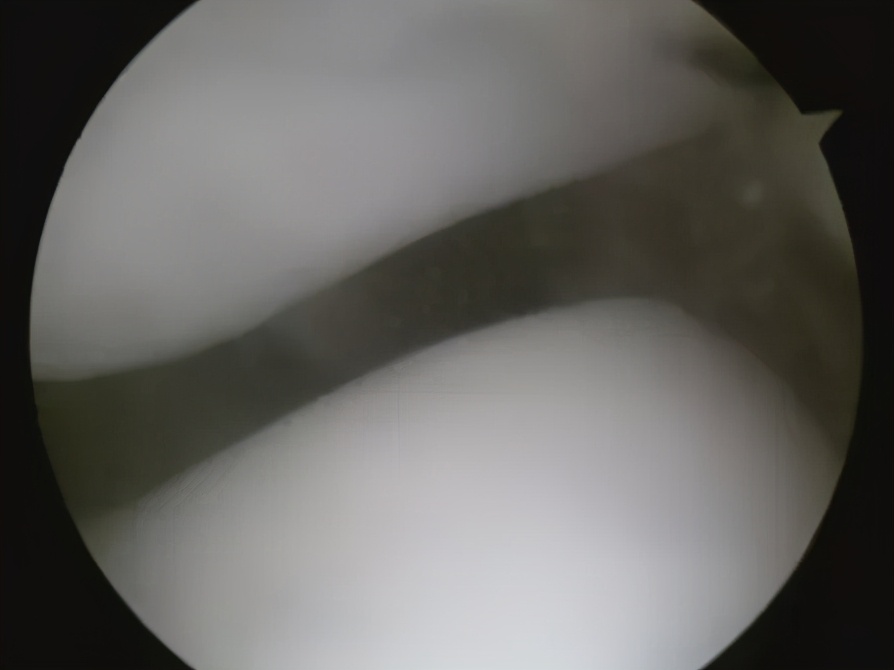

正常的髌股关节

饱经沧桑的髌股关节

髌骨外侧软骨炎

正常人的髌骨应该在正中的轨道跟下面的软骨进行良好的匹配摩擦,但是有很多人因为先天发育不良或后期退变,从而导致髌骨的位置出现了“出轨”的现象,这将导致髌骨外侧的上下软骨面频繁地被磨损,出现软骨炎甚至软骨损伤。

甚至还会出现髌骨脱位,少数髌骨发育严重不良的人,可能会经常出现弯腿时髌骨脱出,伸腿时髌骨又弹回来的奇特景象,这种情况则需要通过矫形重建手术治疗。